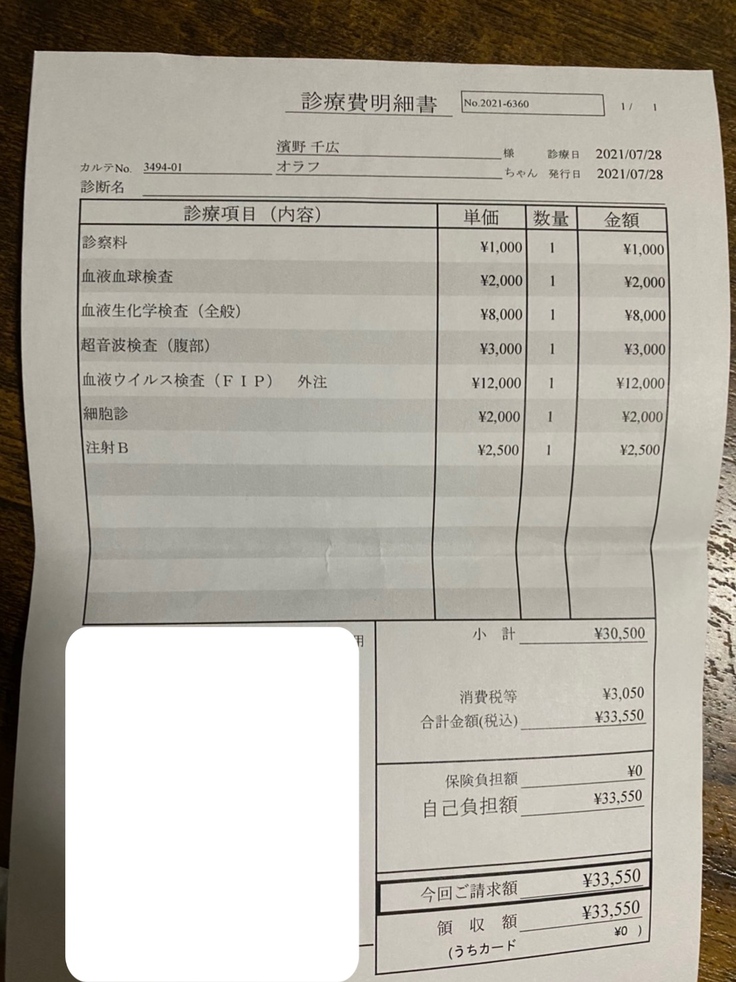

血液検査、超音波検査、FIP検査、細胞診を行いました。

検査費と薬代です。